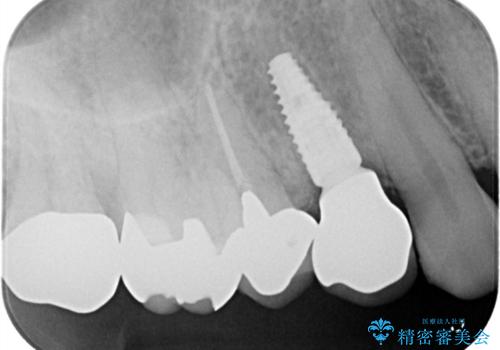

- 「2か月前から歯に違和感があるので診て欲しい」を主訴に来院された患者様です。

被せ物がコア(土台)ごと取れておりかつ根っこも折れてしまっている(歯根破折)状態でした。

歯根破折により保存は不可と診断し抜歯後、骨ができるのを待ってインプラントで治療を行いました。

抜歯後、骨が出来るまで6ヵ月待ちその後インプラントを埋入しました。

アバットメントは患者様の歯肉に合わせて作製するカスタムアバットメントを入れ被せ物はオールセラミッククラウンで被せています。